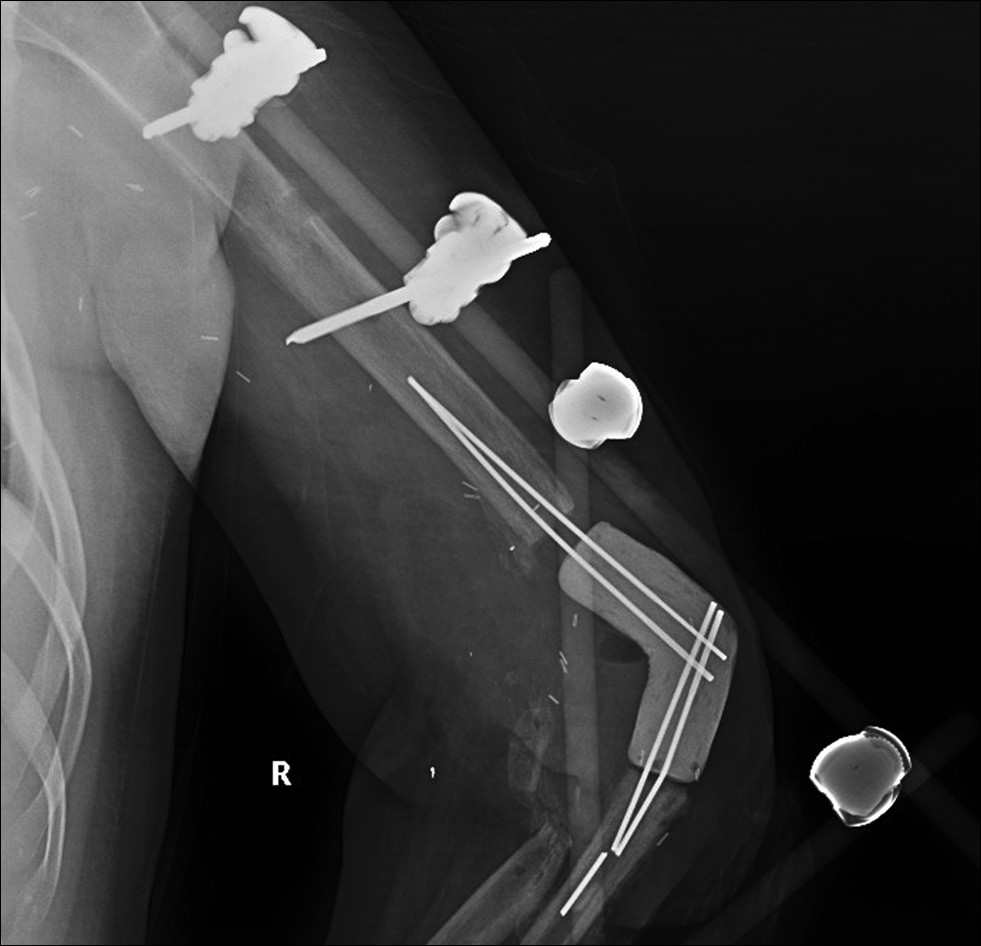

Через 15 недель после получения ранения пациенту выполнено оперативное вмешательство. Положение пациента лёжа на животе, выполнен типичный задний доступ к локтевому суставу размером 18 см, в ране определялся дефект сухожилия трёхглавой мышцы плеча. На протяжении 7 см выполнен невролиз локтевого нерва. По заранее подготовленным шаблонам проведены резекция костей (рис. 14), рассверливание костномозговых каналов плечевой и локтевой кости, имплантация компонентов по технологии «press fit» (рис. 15), подшивание сухожилия трёхглавой мышцы плеча к имплантату. Выполнены установка активного дренажа по Редону, послойное ушивание раны, асептическая повязка, гипсовая иммобилизация в разгибании конечности 160 градусов.

Рис. 14. Пациент Д. Резекция костей по индивидуальным шаблонам: а — плечевой, b — локтевой.

Fig. 14. Patient D. Bone resection using individual templates: a — humerus, b — ulna.